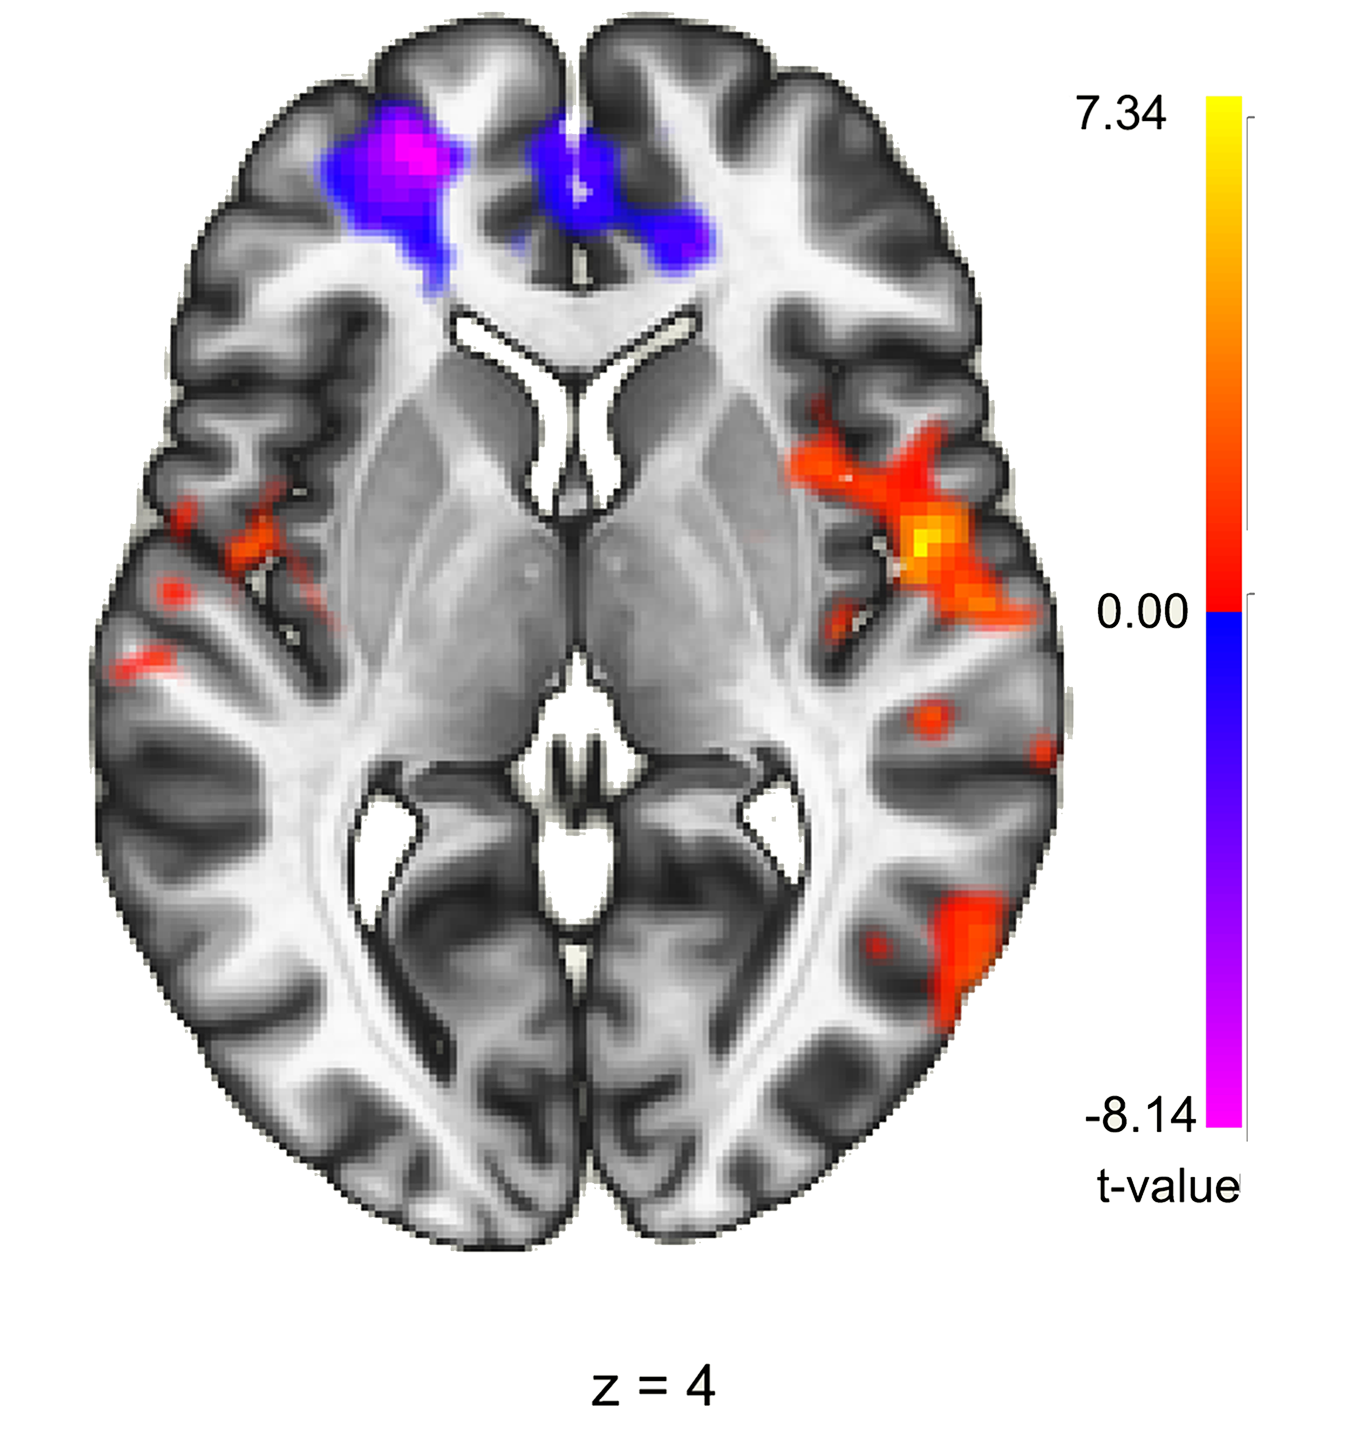

How EcoMeditation Changes Your Brain

High-resolution MRIs and EEGs are now showing us what’s going on in the body and brain of a meditation master.

They have large amounts of the slowest brain waves, alpha, theta and delta, as well as the fastest wave, gamma.

They have small amounts of beta, the signature wave of worry and stress.

Their bodies generate a unique “cocktail” of 7 hormones and neurotransmitters, including pleasure chemicals like serotonin, dopamine and oxytocin. Their nervous systems are firing in “coherence,” relaxed but alert.

The happiness centers of their brains are lit up, while the self-absorbed parts shut down. They are literally in “bliss brain.” Amazingly, when novice meditators follow the 7 steps above, “strong echoes” of these very same changes are observed. (Pennington et al., 2019)